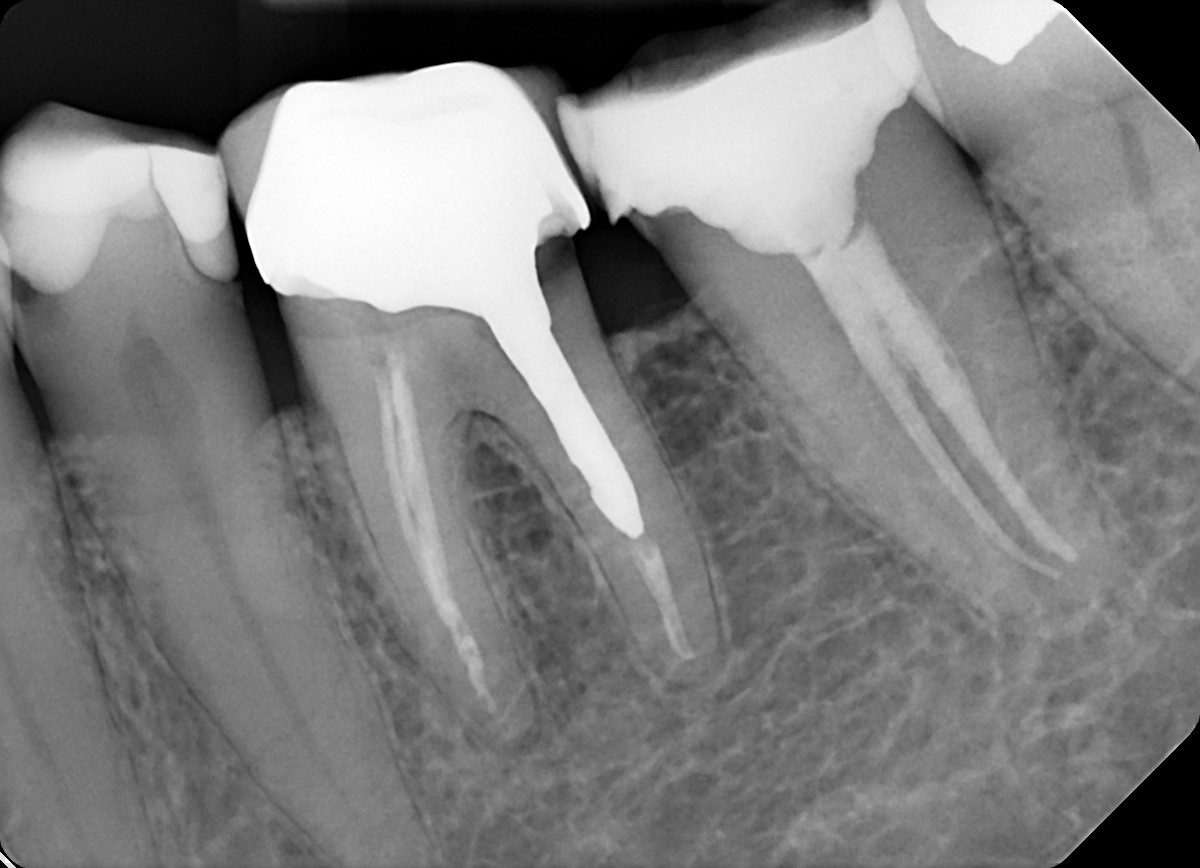

2. What option can be selected for the X ray bellow?